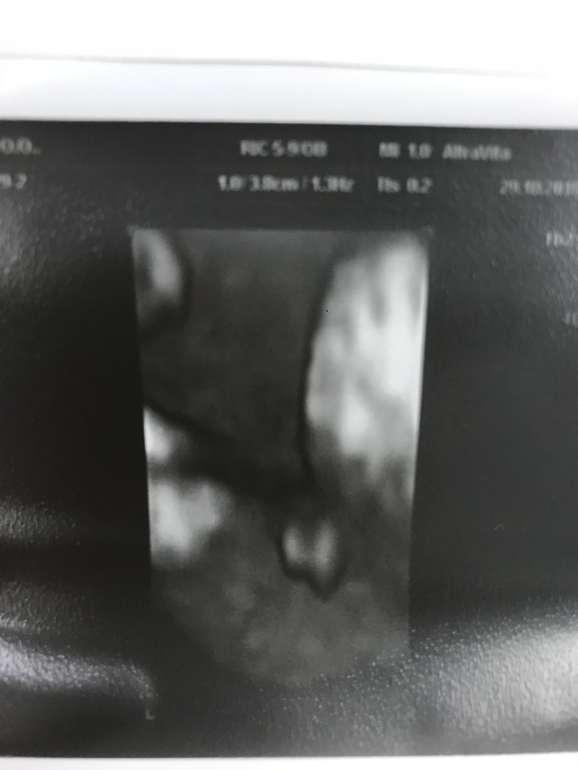

Если смотреть 2 фотку - то половой бугорок горизонтально. Если 1 - то на мошонку это не особо похоже. Яички у мальчиков вообще к году жизни могут опуститься...

а я думаю девочка, губки припухшие на таком сроке нормально, моя дочка даже родилась с припухшими, через недельку только уменьшились )))))))))))) а у мальчишек на узи хозяйство выглядело как кулак с пальцем вверх

, у дочки именно пирожок вот такой виднелся

Сильно как то выпирает. Похоже на мальчика. Сходите в 16-17 недель, точно уже увидят.)

Это моё, может не очень удачное фото, сделанное под попкой, видно кофейное зернышко? Две дольки мандаринки. 💖